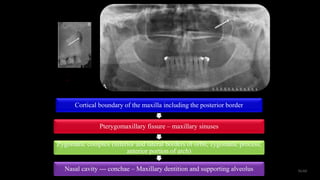

Midfacial region

Cortical boundary of the maxilla including the

posterior border

Pterygomaxillary fissure – maxillary sinuses

Zygomatic complex (inferior and lateral borders of

orbit, zygomatic process, anterior portion of arch)

Nasal cavity --- conchae – Maxillary dentition and

supporting alveolus

Cortical boundary of the maxilla including the posterior border

Zygomatic complex (inferior and lateral borders of orbit, zygomatic process,

anterior portion of arch)

Nasal cavity --- conchae – Maxillary dentition and supporting alveolus